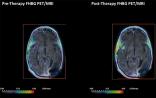

日前,发表在《科学转化医学》杂志上的一项研究中,来自斯坦福大学的科学家们首次发现了一种能够可视化和监测T细胞免疫疗法在体内作用过程的成像技术。这项工作是在患一种致命脑癌的病人中进行的。但研究人员强调,这一突破性的技术能够用于追踪靶向任何种类癌症的免疫细胞。